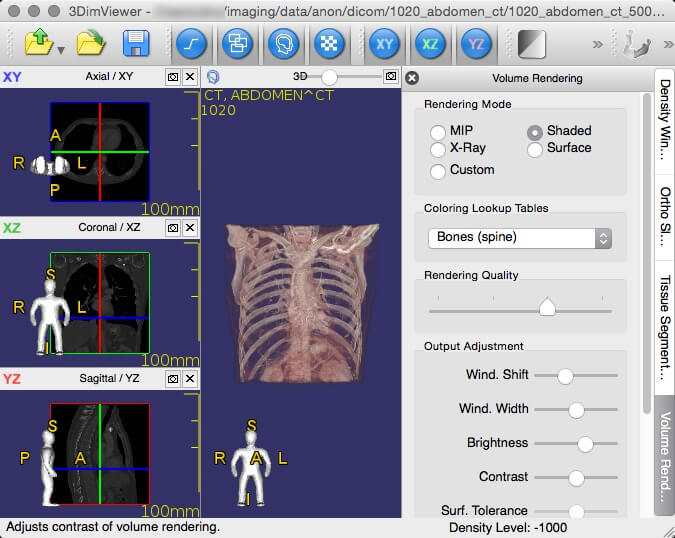

3. 3DimViewer

3DimViewer is a cross-platform lightweight 3D viewer for DICOM datasets written in C++. It is open source with a feature set that includes orthogonal and multiplanar XY, XZ, and YZ views, an adjustable density window, importing multiple DICOM datasets, 3D visualization of CT and MRI scans, surface modelling of any segmented tissue, 3D surface rendering, etc.